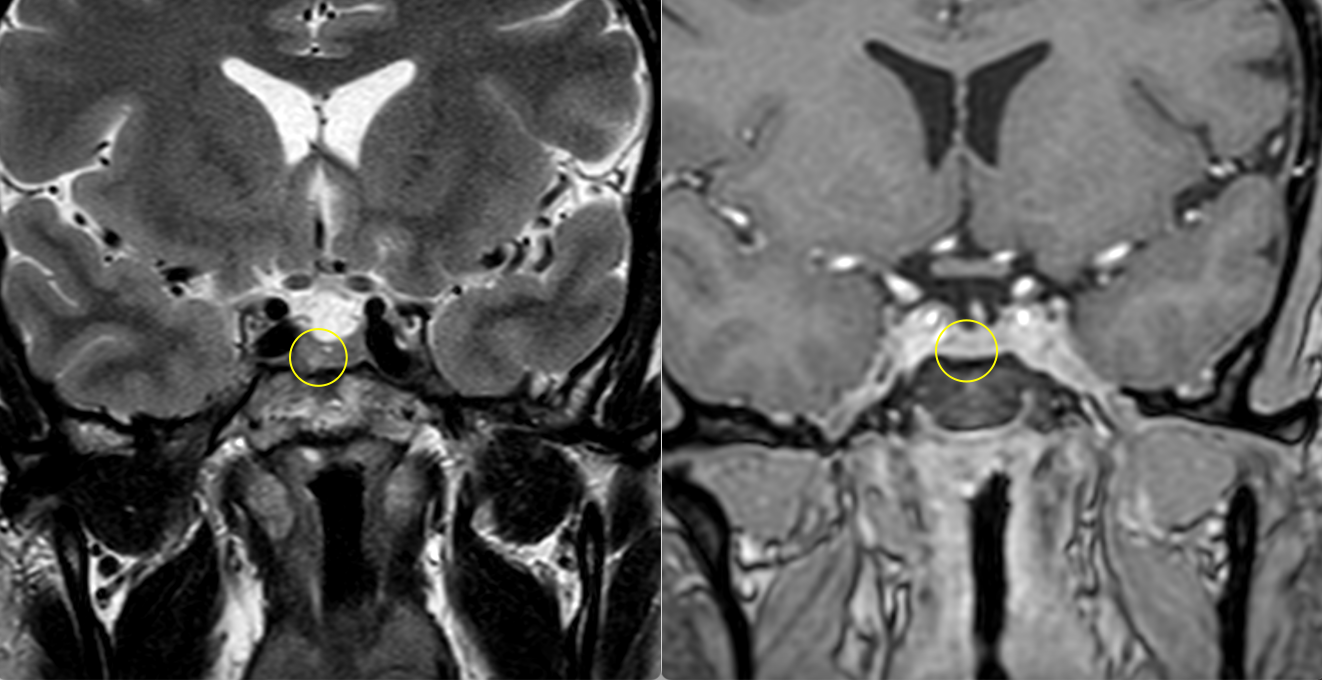

- Microadenoamele necesită un tip special de examinare RMN, cu secvențe repetate (în dinamică) realizate după administrarea substanței de contrast. Ele apar de obicei ca niște defecte de umplere – mici zone ne-gadolinofile (glanda hipofiză normală capteaza contrast mai repede decât adenomul); alteori singurul indiciu despre existența și localizarea adenomului (în afară de analizele hormonale) îl constituie asimetria glandei cu devierea tijei hipofizre de partea opusă